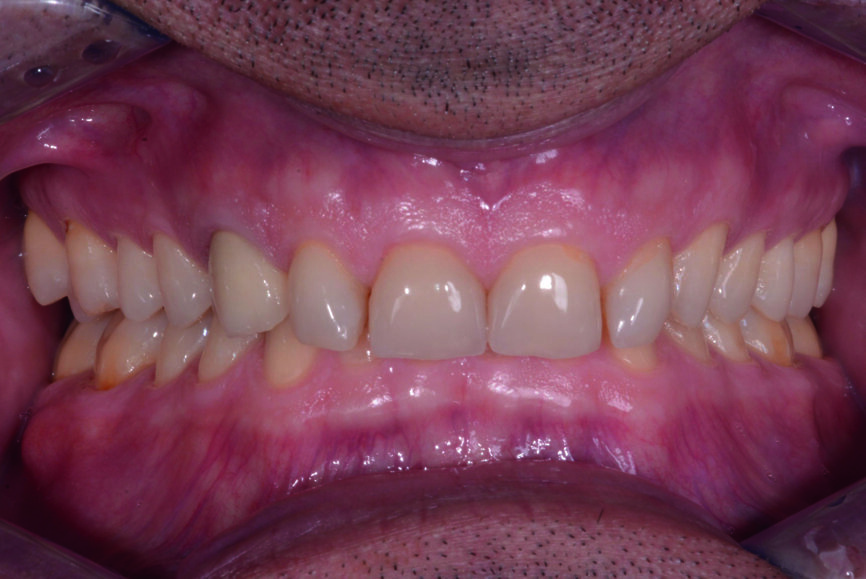

Fig. 7 : Deux ans plus tard, avant le traitement (2017).

En 2017, le patient revient au cabinet pour terminer le traitement (Fig. 7), et une empreinte numérique intraorale est de nouveau réalisée (scanner Carestream 3600). Pour préparer les dents piliers, un second mock-up en résine bisacrylique (Structur 3, VOCO) est fabriqué dans une imprimante 3D (SolFlex, VOCO) à l’aide d’une matrice formée sous vide (V-Print Ortho, VOCO). Le travail est accompli par une technique minimalement invasive en fonction du mock-up (Fig. 8).